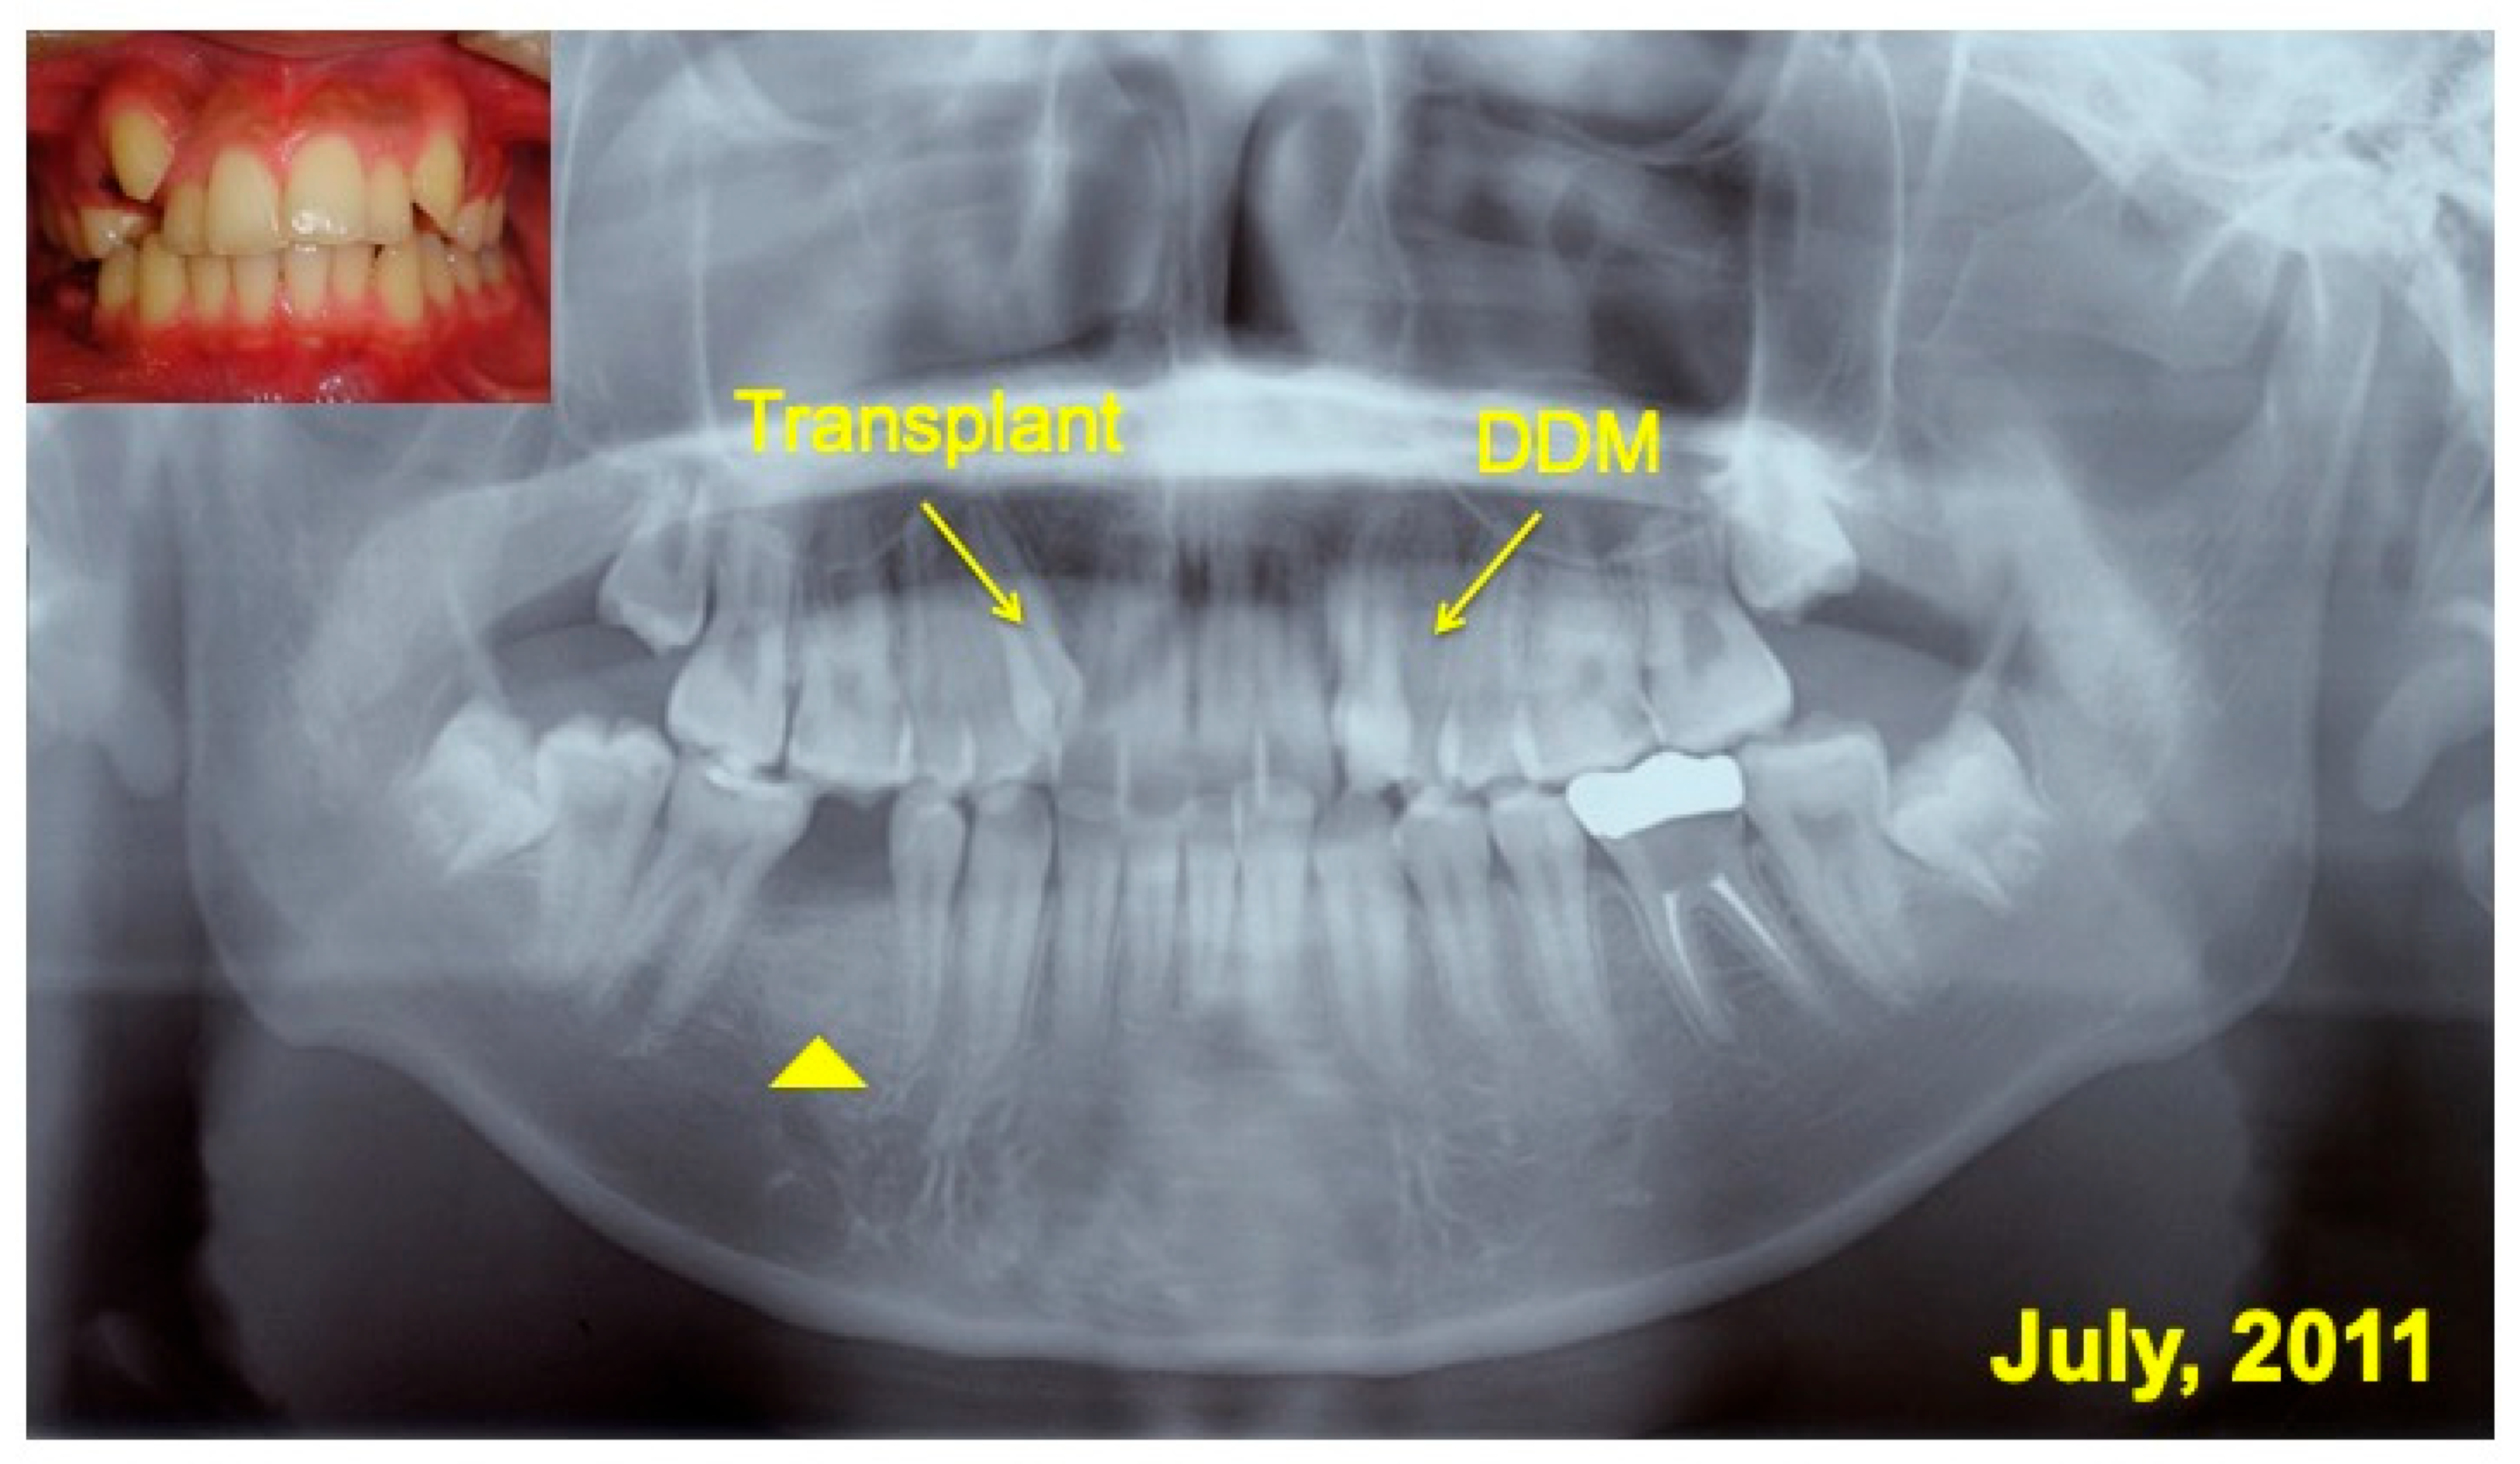

A 16 year-old-male was introduced from a private orthodontic dental clinic to our dental unit in 2011. The patient presented with a congenital missing lower left second premolar (#45), examined on initial panoramic X-ray photo (Figure 1). He had lost a milk tooth (#4E) a few weeks previously. Clinical diagnosis revealed a congenital missing tooth (#45), crowding, and maxillary protrusion. His medical history was unremarkable.

Figure 1.

Initial views of panoramic X-ray photo and oral before orthodontic treatment. Arrows indicating #14 for transplant and #24 for pDDM. Arrowhead showing congenital missing tooth (#45).